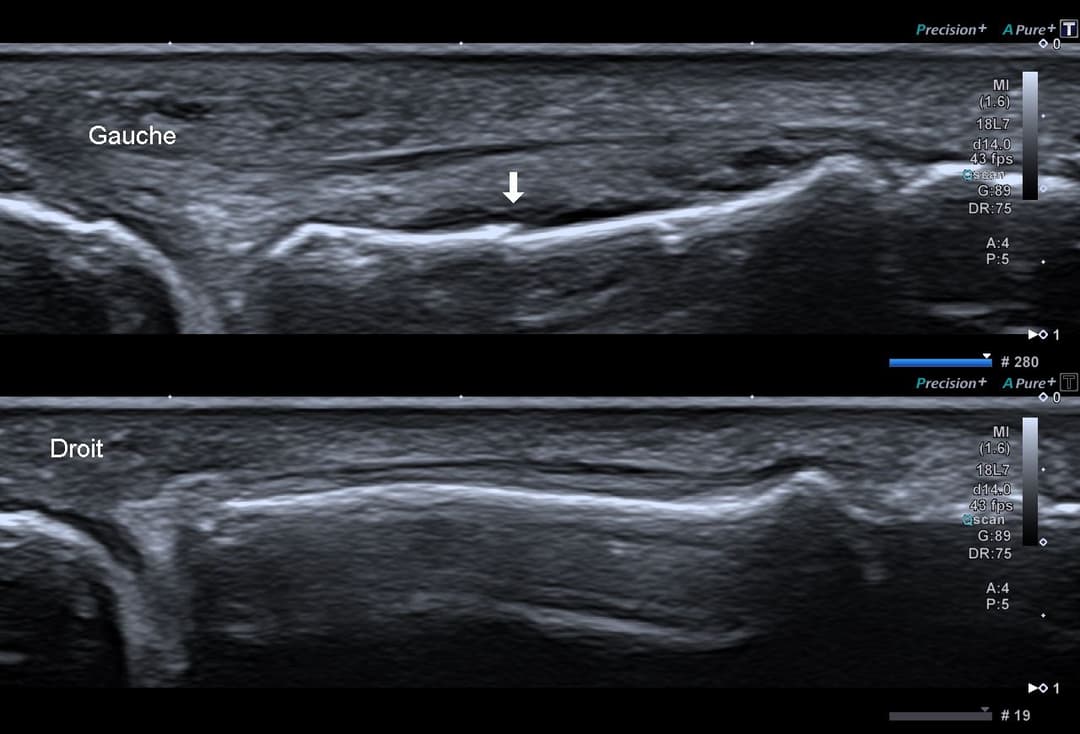

Fracture instable étudiée en échographie dynamique

Etude dynamique montrant l'instabilité de la fracture

L'échographie permet de rattraper des radiographies interprétées initialement comme normale, en explorant finement via une échopalpation de la zone douloureuse la corticale osseuse.